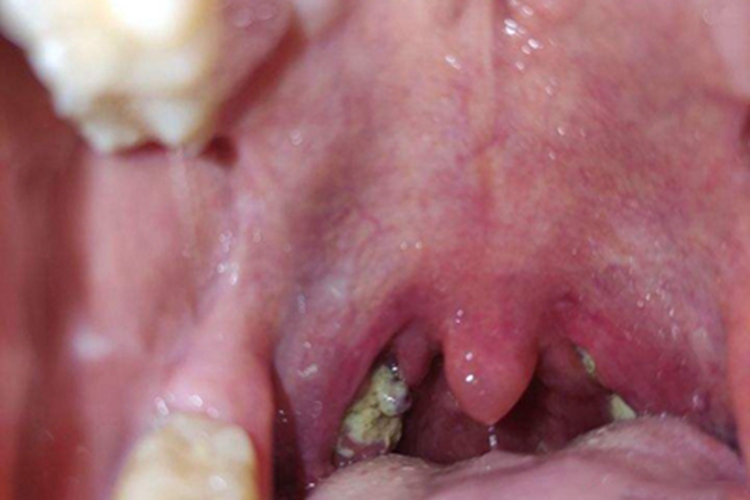

化脓性扁桃体炎检查可见患者的扁桃体化脓,表面有黄白色小脓点,同时可伴有高热、全身不适等症状,常由溶血性链球菌感染引起。

化脓性扁桃体炎常导致患者的扁桃体受累,引起化脓,检查可见表面有黄白色小脓点,或有黄色脓性分泌物,其脓性分泌物可连接成片,呈伪膜状,边界清晰,易擦去。同时患者还可伴有咽痛吞咽时加重、高热、全身不适等症状。